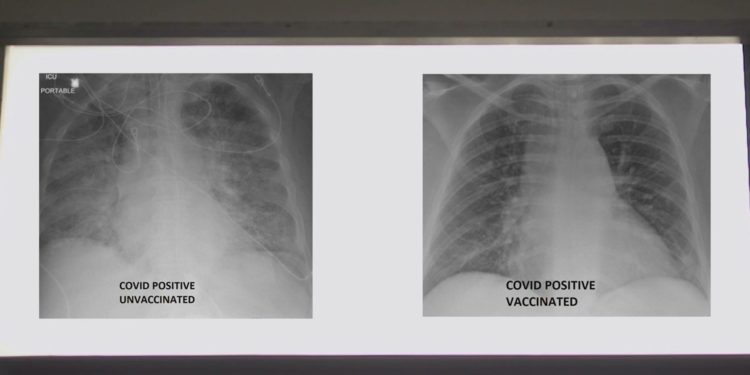

Aşıların etkisini gözler önüne sermek isteyen doktor, iki röntgen gösterdi. Röntgen fotoğraflarından biri Covid-19 aşısı yaptıran bir hasta diğeri ise aşı yaptırmayan bir hastaya aitti.

Dr. Kamel akciğerlerde görünen beyaz noktaların virüs olduğunu belirtirken, hasta bilgilerini korumak için daha fazla ayrıntı vermedi.

Röntgeni inceleyen doktor, aşı yaptırmayan hastanın büyük bir ihtimalle oksijen desteğine ihtiyacı olacağını söyledi.